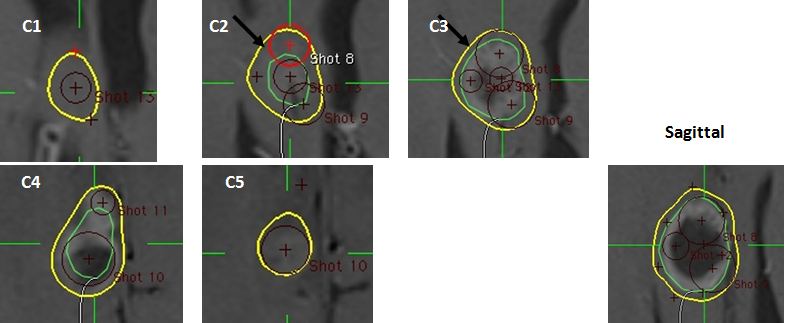

Bệnh nhân Bùi văn U., nam, 26 tuổi. Chẩn đoán U tuyến tùng, chỉ định xạ phẫu dao gamma quay (RGK) liều 16Gy”

Hình 3: Hình ảnh A, B: đặt shot ở giáp đường biên khối u; C: đặt shot ở xa đường biên khối u

Bệnh nhân Bùi văn U   nam 26 tuổi, chẩn đoán U tuyến tùng, chỉ định xạ phẫu dao gamma quay (RGK) liều 16Gy”